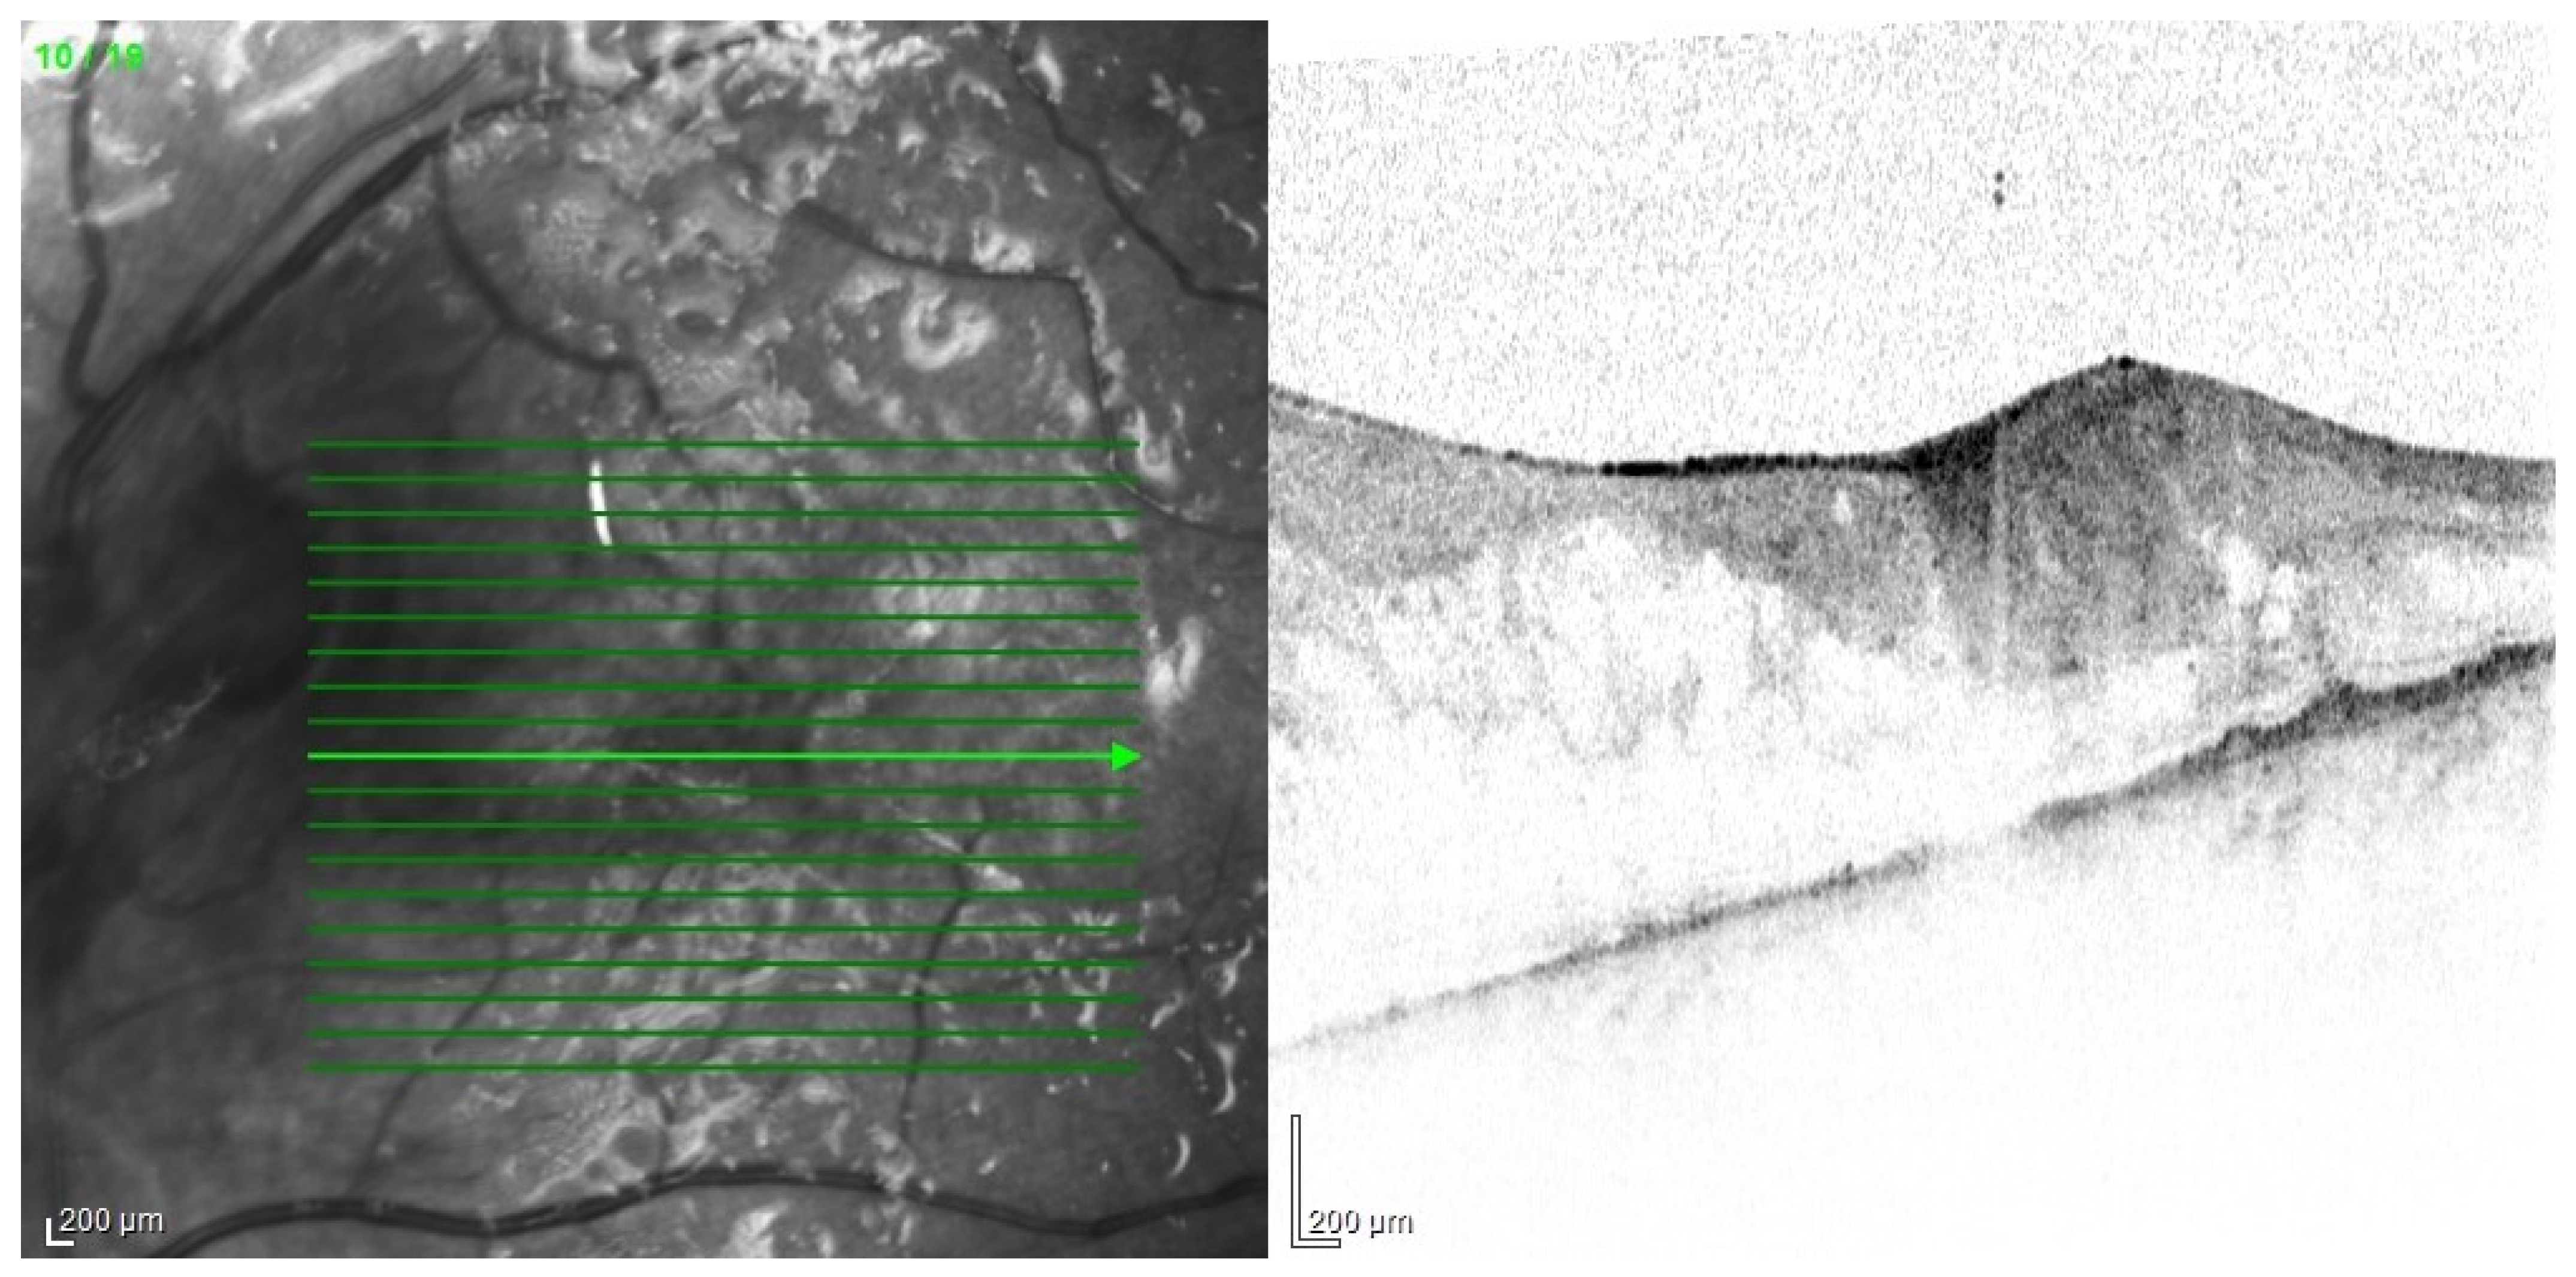

Based on the clinical picture in the ophthalmological examination and the dynamics of the course of EE, certain conclusions about the etiology of the infection can be drawn. Bacterial infections proceed usually in acute while fungal infections in subacute manner. In fungal infections, characteristic cotton-like foci on the retina and in the vitreous body often appear, often in the form of “strings of pearls” (Figure 11). Optical coherence tomography enables fully accurate imaging of single inflammatory foci, as long as the transparency of the optical centers remains at an appropriate level (Figure 12).

Figure 12.

OCT examination of the patient presented in Figure 11. Scan through the retinal foci. There are also visible numerous densities in the vitreous.